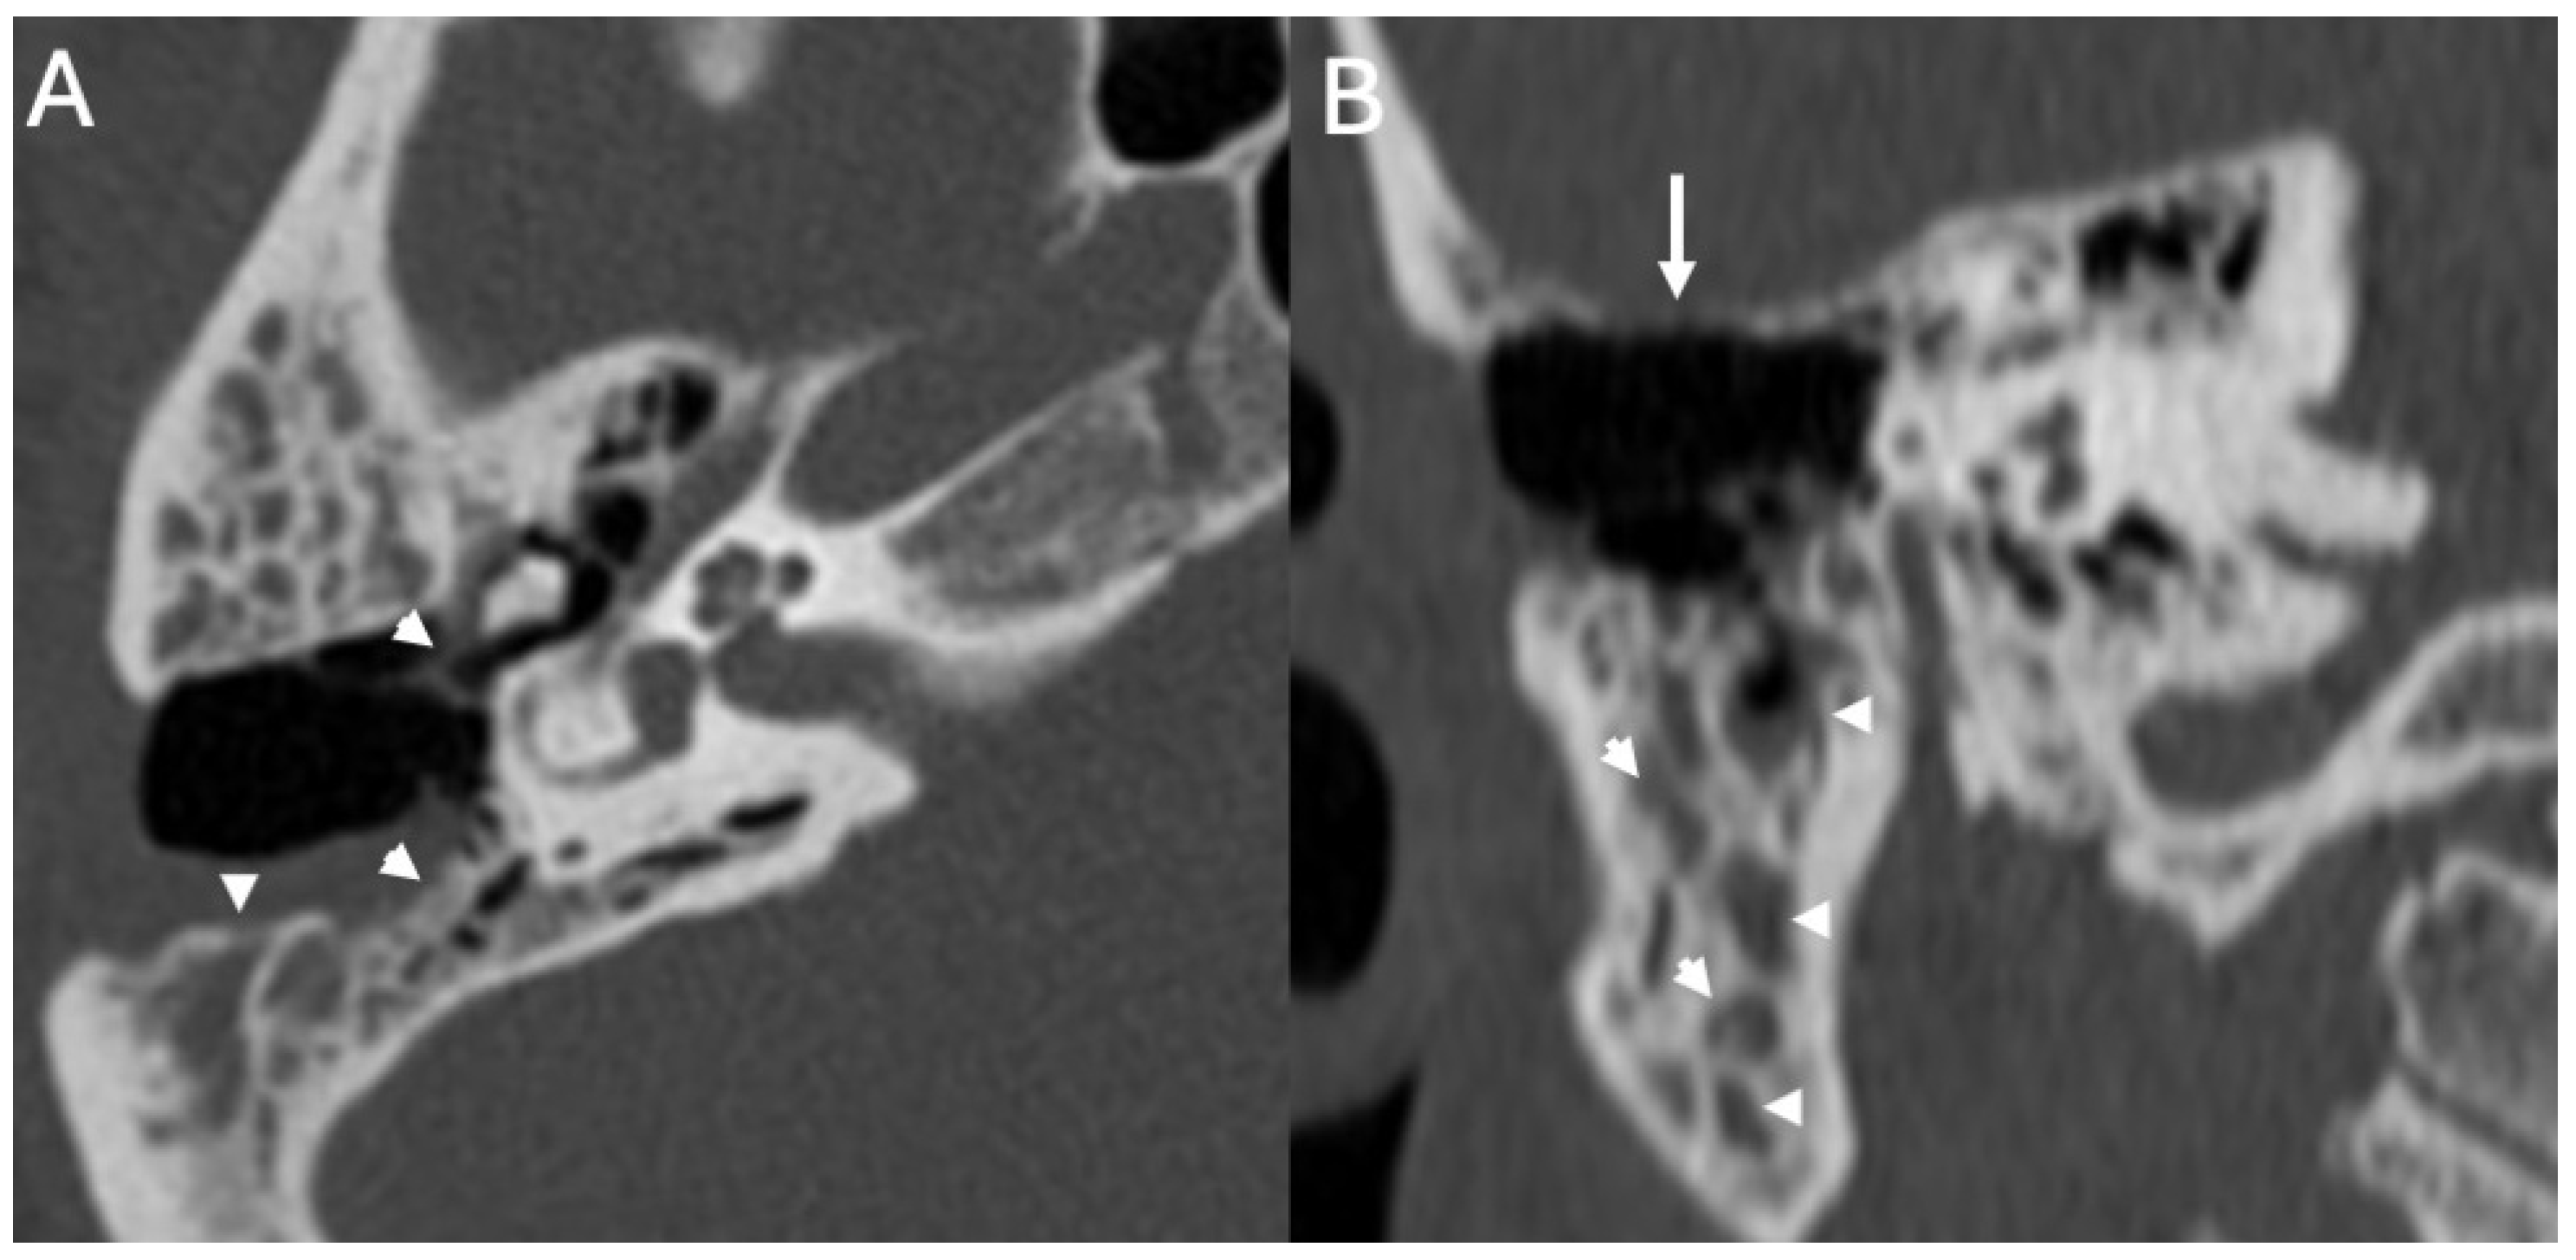

3.2. Bony Dehiscence

| Bony Dehiscence/Temporal Bone Defects | Barbara et al., 2022 [22]; Sanna et al., 2009 [23]; Lim et al., 2012 [24]; Rabiei et al., 2025 [25] | Case-based studies and reviews | Tegmen tympani or semicircular canal defects create a route for meningitis and meningoencephalocele; HRCT coronal reconstructions preferred. |